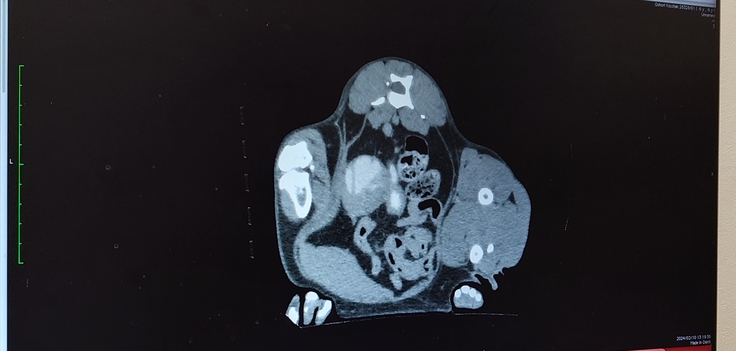

🐈造影剤を流して、腎臓から膀胱にちゃんと詰まらずに流れて行くか、膀胱から腎臓に逆流しないかを調べてもらいました。🐈

🐈尿管は拡張したままで腎盂も肥大したままではあるんだけど、造影剤は途中で詰まったり、逆流したりすることもなく、膀胱に流れていたから大丈夫とのことで安心しました🐈

🐈血液検査ではまた白血球等の数値が高くなっていて、また尿路感染を起こしているかもしれないと説明を受けました。🐈

🐈腎臓に関する数値は正常値だったので良かったです。🐈

今日はヨッちゃんが麻酔をしているから培養検査が出来ないので、こちらからもかかりつけの動物病院の先生に電話しておくので1週間後にかかりつけの動物病院で検査してもらってくださいとのことでした。もう1つ、ヨッちゃんは尿路感染を繰り返し起こしやすいかもしれなくて定期的に感染していないか検査をしていた方が良いことと、将来的に腎臓に膿が溜まってしまうかもしれない。もし、腎臓に膿が溜まってしまったら腎臓の摘出手術をすることになってしまうんです。という説明を受けました。もう1つの腎臓と膀胱をつなぐSUBシステムの手術の選択肢を言われるのかと思いきや腎臓摘出。えーー。。と複雑な感情になりました😨😵😱